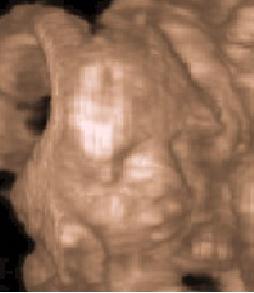

Vagány a csajszikád!